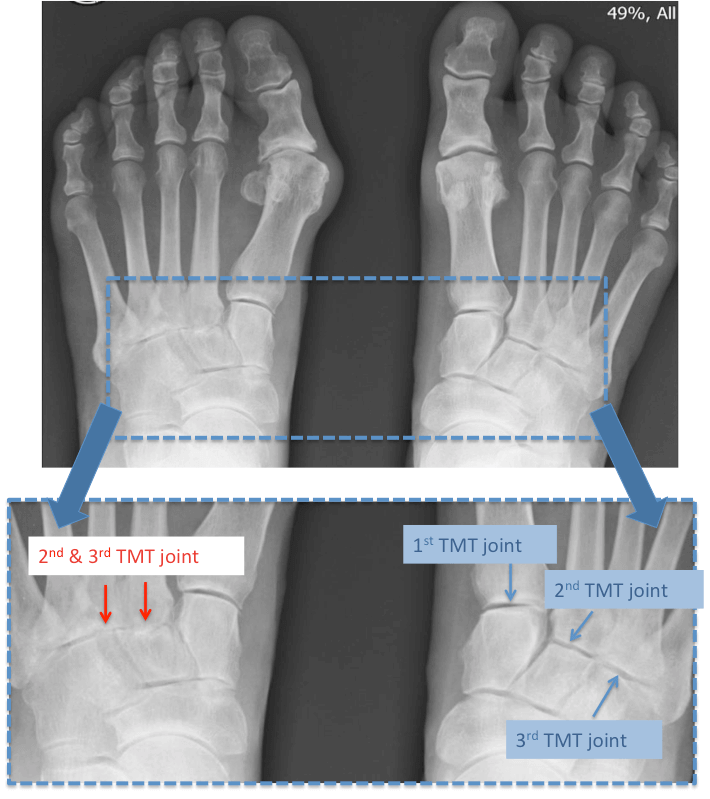

Midfoot Arthritis Mr Malik Orthopaedic Consultant LFAC Arthritis In Top Of Foot X Ray Naviculocuneiform joint, intercuneiform joints, and metatarsal cuneiform joints. Midfoot arthritis is defined as arthritis of the midfoot which includes the following joints: The main symptoms of midfoot arthritis are swelling, redness and pain at the top and middle portion of the foot. Signs of arthritis include pain, stiffness and a reduced. Often, these symptoms begin seemingly at random;. Arthritis can. Arthritis In Top Of Foot X Ray.